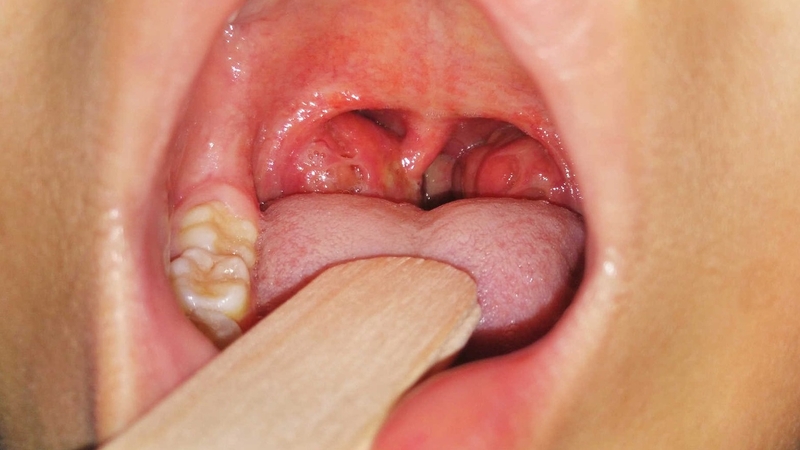

Viêm amidan cấp tính là tổn thương viêm sung huyết hoặc viêm mủ của tuyến amidan khẩu cái. Nếu do virus gây bệnh amidan cấp tính thường là nhẹ, trái lại nếu gây bệnh da vi khuẩn thì bệnh nặng.

Gợi ý cách chữa viêm họng amidan tại nhà hiệu quả 1Viêm amindan cấp tính do virus gây bệnh thường là nhẹ

Viêm amidan cấp tính thường gặp ở trẻ có độ tuổi 5 - 15 tuổi. Triệu chứng bao gồm: